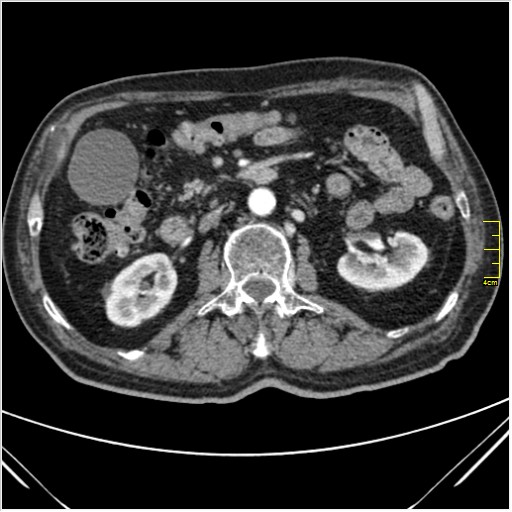

Мужчина 62 года с желтухой

Опухоль головки поджелудочной железы, расширение холедоха и панкреат. протока (Double Channel sign)

Карциномы панкреас гиподенсны на КТ с болюсом, т.к. содержать много соединительной и фиброзной ткани, в отличие от нормальной ткани железы, которая (как любая железа) хорошо васкуляризирована. Поэтому если видим в панкреас солидное гиподенсное образование - всегда настораживает на предмет рака. Второй момент: обязательная оценка взаимоотношения опухоли к ВБА и ВБВ, на предмет оценки операбельности.